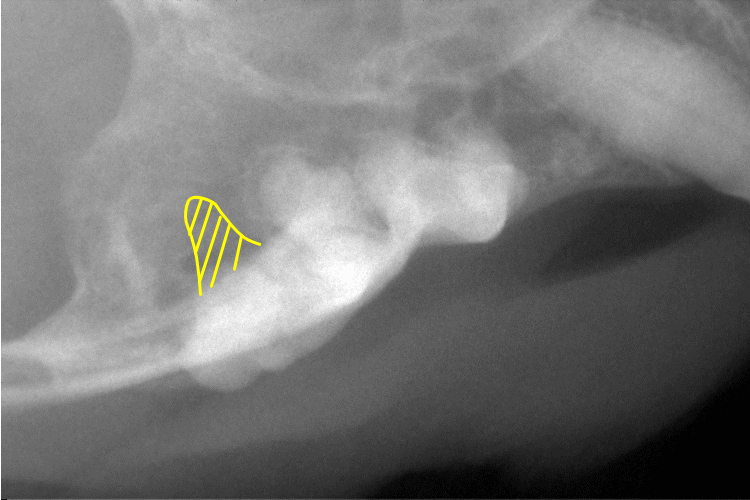

歯科レントゲン

右上顎第3前臼歯です。

遠心根が溶けて無くなっていることが確認できます。